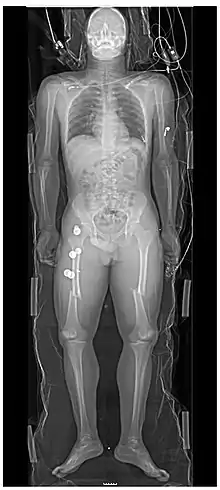

Projectional radiography, also known as conventional radiography,[1] is a form of radiography and medical imaging that produces two-dimensional images by X-ray radiation. The image acquisition is generally performed by radiographers, and the images are often examined by radiologists. Both the procedure and any resultant images are often simply called 'X-ray'. Plain radiography or roentgenography generally refers to projectional radiography (without the use of more advanced techniques such as computed tomography that can generate 3D-images). Plain radiography can also refer to radiography without a radiocontrast agent or radiography that generates single static images, as contrasted to fluoroscopy, which are technically also projectional.

- Hard tissues such as bone require a relatively high energy photon source, and typically a tungsten anode is used with a high voltage (50-150 kVp) on a 3-phase or high-frequency machine to generate bremsstrahlung or braking radiation. Bony tissue and metals are denser than the surrounding tissue, and thus by absorbing more of the X-ray photons they prevent the film from getting exposed as much.[11] Wherever dense tissue absorbs or stops the X-rays, the resulting X-ray film is unexposed, and appears translucent blue, whereas the black parts of the film represent lower-density tissues such as fat, skin, and internal organs, which could not stop the X-rays. This is usually used to see bony fractures, foreign objects (such as ingested coins), and used for finding bony pathology such as osteoarthritis, infection (osteomyelitis), cancer (osteosarcoma), as well as growth studies (leg length, achondroplasia, scoliosis, etc.).

- Soft tissues are seen with the same machine as for hard tissues, but a "softer" or less-penetrating X-ray beam is used. Tissues commonly imaged include the lungs and heart shadow in a chest X-ray, the air pattern of the bowel in abdominal X-rays, the soft tissues of the neck, the orbits by a skull X-ray before an MRI to check for radiopaque foreign bodies (especially metal), and of course the soft tissue shadows in X-rays of bony injuries are looked at by the radiologist for signs of hidden trauma (for example, the famous "fat pad" sign on a fractured elbow).